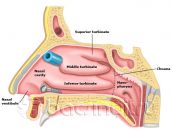

Bệnh viêm xoang là một tình trạng phổ biến, khiến cho các xoang và đường mũi bị đỏ và đau (viêm). Tình trạng này có thể khiến người bệnh rất khó chịu, không thể sinh hoạt như bình thường. Vậy đâu là nguyên nhân và cách điều trị viêm xoang? Mời bạn tham khảo bài viết sau đây.

Bệnh viêm xoang hàm là một dạng viêm xoang phổ biến, xảy ra khi lớp niêm mạc bao phủ xoang hàm bị viêm nhiễm. Để hiểu rõ hơn về triệu chứng, nguyên nhân và cách điều trị của bệnh, mời các bạn tham khảo bài viết dưới đây!

Trong nhiều năm trở lại đây, viêm xoang đã trở thành một trong những vấn đề nhiễm trùng phổ biến. Tình trạng viêm này phát sinh ở các hốc xoang cạnh mũi, nơi sản xuất chất nhầy cần thiết cho đường mũi hoạt động hiệu quả. Trong một số trường hợp, vấn đề trên còn có nguy cơ dẫn đến nhiễm trùng xương hay thậm chí là viêm màng não. Cùng tham khảo bài viết ngay sau đây để biết nguyên nhân và cách điều trị hiệu quả nhé!